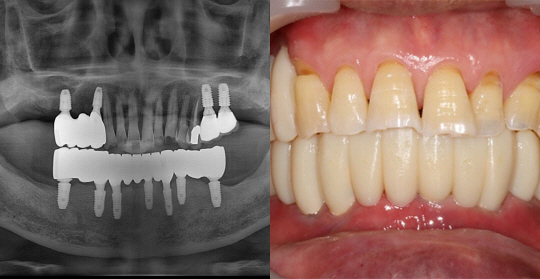

(63세 남 환자)